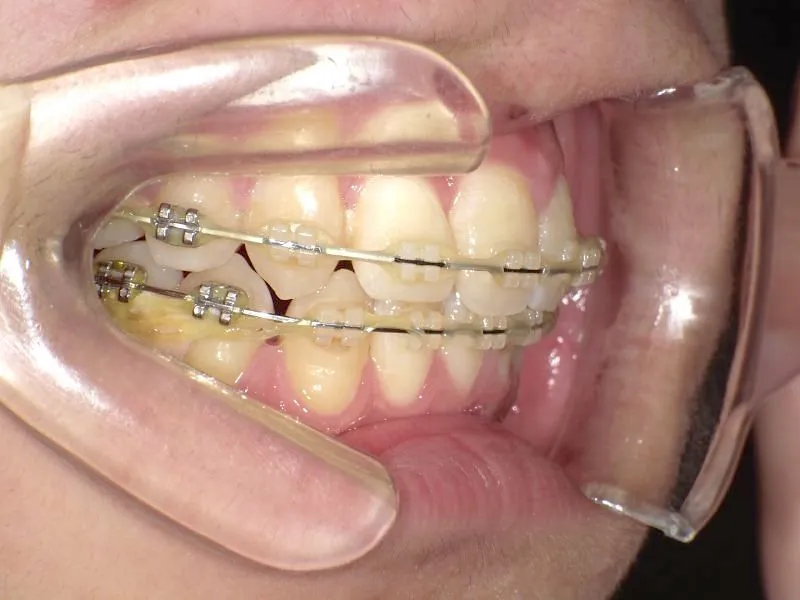

治療経過1